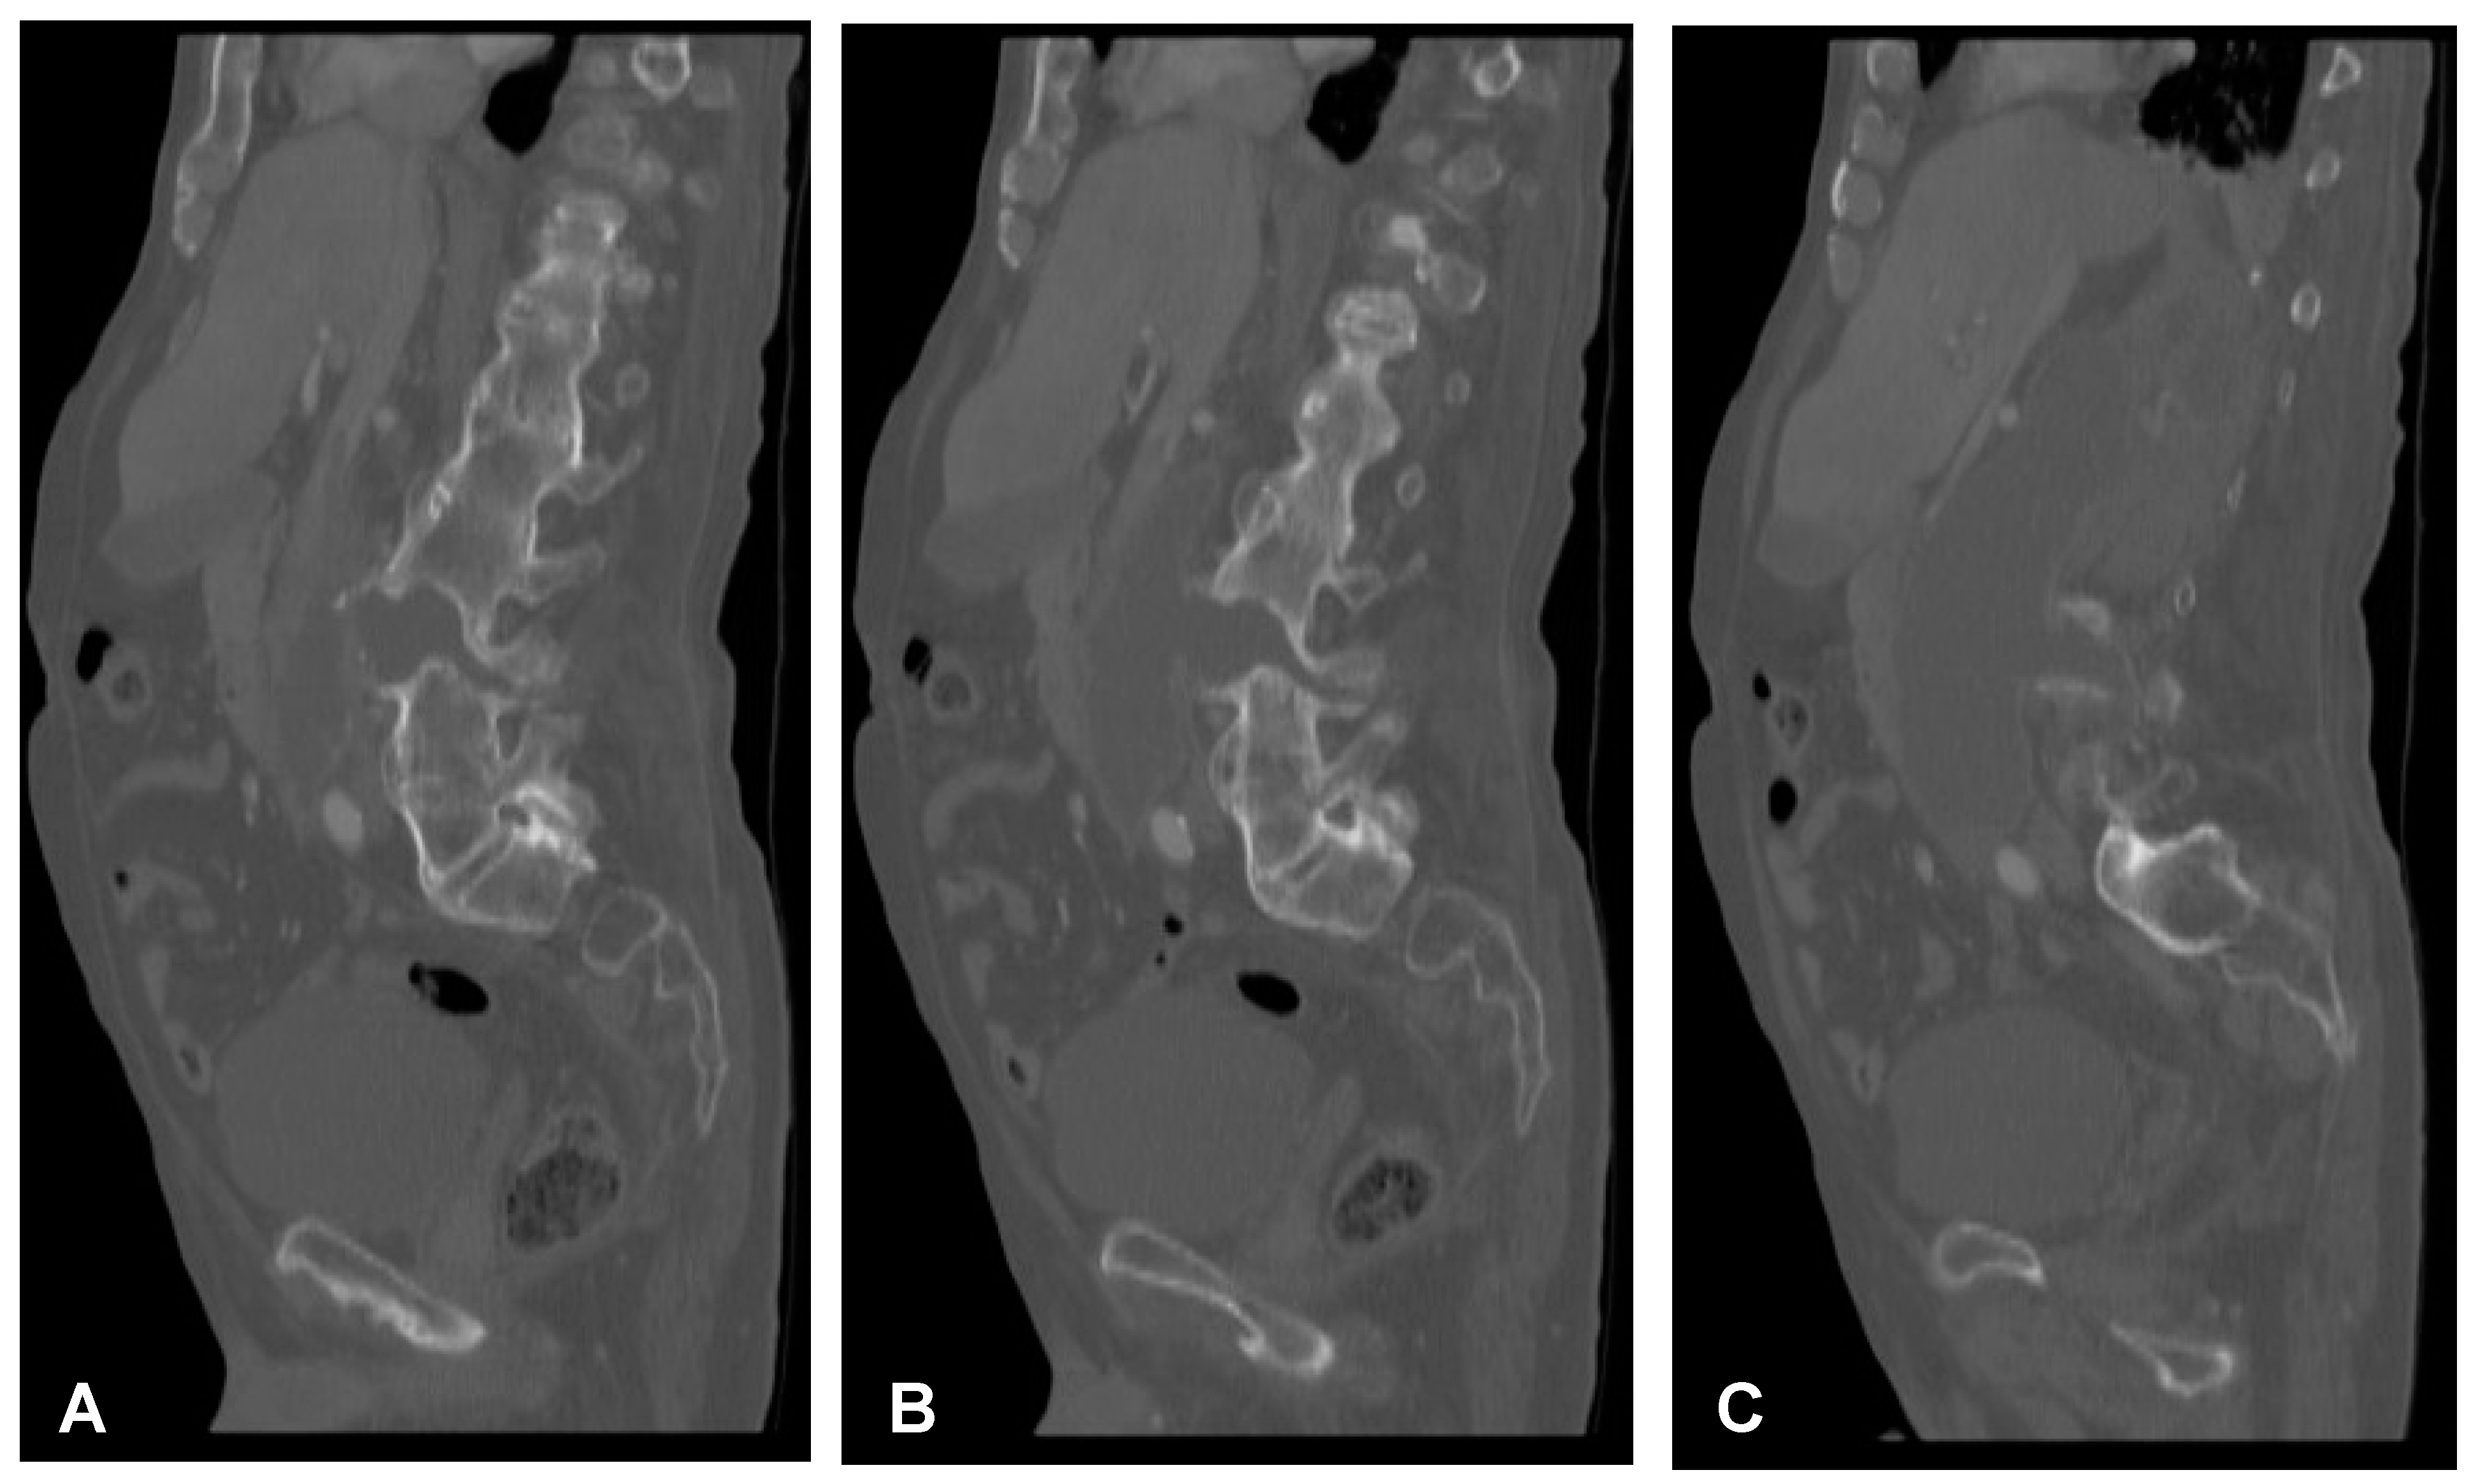

Figure 2. Preoperative sagittal (AC) and axial (D,E) CT scans (non-contrast enhanced) of the lumbar spine demonstrating hypodense area at the L3/L4 intervertebral disc space communicating with both psoas major muscles forming massive well-defined fluid-like collection in the right retroperitoneum.

A 59-year-old man presented to the hospital with atypical abdominal pain for a few days, three weeks after sustaining a low-energy fall. At the time of admission, the patient had normal upper and lower extremity strength and no pathologic reflexes, as well as no bowel or bladder incontinence. The initial performed plain radiograph of the abdomen demonstrated a fracture line completely slicing through the L3/L4 intervertebral disc space and features of ASH (Figure 1). The additional performed computed tomography (CT) scans demonstrated a three-column fracture of L4 vertebrae with a suspicious transdiscal injury at the L3/L4 level, which was morphologically classified as type B3/C according to the Arbeitsgemeinschaft für Osteosynthesefragen (AO) spine classification. Moreover, at the fracture level, the hypodense area communicating intervertebral disc space with both psoas major muscles forming a massive, well-defined fluid-like collection in the right retroperitoneum was observed (Figure 2). In addition, contrast-enhanced CT (CE-CT) showed a thick enhancing wall and internal septae within an area measuring a total of 10 cm × 20 cm × 10 cm (TR × AP × CC) (Figure 3). Furthermore, the performed magnetic resonance imaging (MRI) scans confirmed the cystic nature of the lesion, which had no specific characteristics and demonstrated intensities that were similar to those of cerebrospinal fluid (CSF) (Figure 4). Taking into consideration the history and radiological features, suspicion of spondylodiscitis with osteomyelitis features and retroperitoneal abscess formation was provided by the radiologist. Blood analysis performed on admission revealed the following results: hemoglobin (Hb): 9.6 g/dL; platelet (PLT): 192 × 109/L; white blood cell (WBC): 9.7 × 109/L; and creatinine (CREA): 0.42 mg/dL. Despite the lack of infection symptoms, the patient was empirically administered intravenous antibiotics, including meropenem (1 g every 8 h) and vanomycin (1 g every 12 h), without waiting for microbiological confirmation.